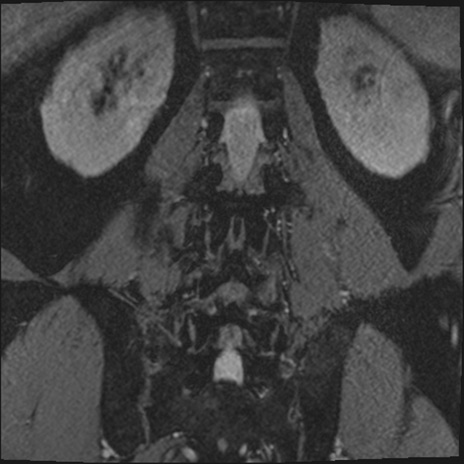

【整形】TIPS症例2 腰椎MRI 3D(冠状断像)

【症例】70歳代男性

【主訴】左下肢痛

【現病歴】2週間前くらいから腰痛、左下肢痛あり。左臀部から大腿、下腿外側のしびれが常時ある。歩行とともに同部位の痛みあり。

【身体所見】Lasegue70-/60+、Bragard-/±、PTR ±/±、ATR -/-、IP 5/5、TA 5/4、TS 5/5、EHL 右第1足趾なし/3、FHL 5/5、hypersthesia(-)、足背動脈触知良好

異常所見と診断は?